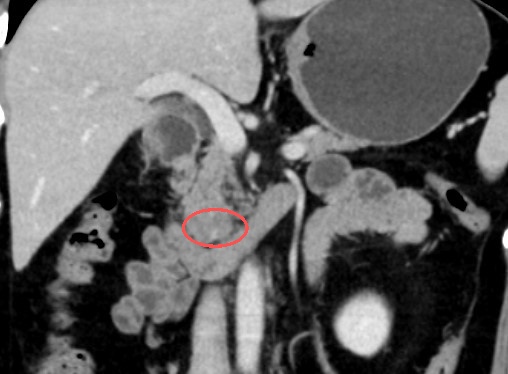

来院后,进一步的影像学检查揭开了这颗隐匿肿物的真面目:疑似胰腺实性假乳头状瘤,直径约2.5厘米,仅一枚一元硬币大小。“肿瘤与重要血管紧密交织,即便是在传统开腹手术的直视下,显露和分离都极其困难,稍有不慎就会面临难以控制的大出血。”程庆保主任介绍道。

胰腺钩突隐匿于腹腔极深处,不仅操作空间极其逼仄,紧密包绕着肠系膜上动静脉,更为众多的致命大血管所包绕。这里神经淋巴密集,肿瘤极易与周围脏器致密粘连,医生必须在极其狭小的缝隙里“走钢丝”,既要精准剥离血管、防范大出血,又要完成彻底的清扫,堪称外科手术的“生命禁区”。